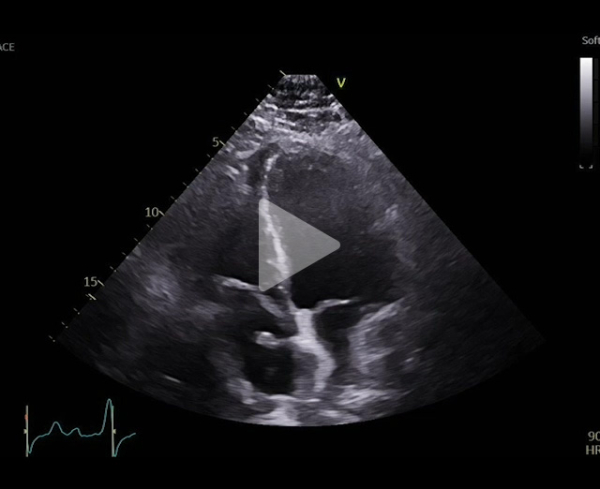

Vidéo 2

Consultation de contrôle à 6 mois, régression franche de la dyspnée (avril 2025)

Bilan de dyspnée en 2024 : syndrome platypnée-orthodéoxie

Découverte de Foramen Oval Perméable avec shunt droit -gauche massif

- Décision de fermeture devant caractère symptomatique : fermeture percutanée en 10/2024 dont les suites sont simples , permettant une amelioration de la symptomatologie